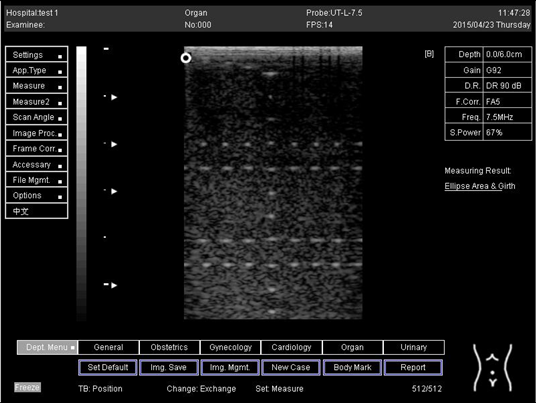

18.0Lateral resolution

Biomimetics 07 00130 i020

D1 = 5.0

D2 = 4.1